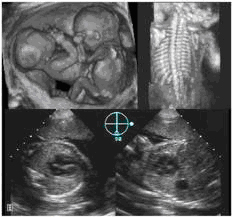

Compliance Consultants has accomplished many Ultrasonic Imaging

systems that offer an array of diagnostic possibilities. An ultrasonic

imaging system consisting of an integral transducer & catheter that connect

to an ultrasonic transmitter/receiver. This system provides a diagnostic

session to image, display, store and publish patient diagnostic images. This

is a prescription device used for orthopedic or pathological imaging. The

catheter is inserted into the patient at the region of interest via a surgical

procedure. The diagnostic session allows the physician to image joints,

ligaments or tendons by less invasive means than traditional diagnostic

methods.